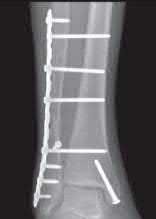

A 64-year-old woman is thrown off a horse, sustaining the injury shown in Figures A and B. She undergoes surgical fixation as seen in Figures C through E. What is the most commonly reported complication of this procedure?

The patient in the scenario has a 2-part proximal humerus fracture treated with a locking plate as seen in Figures A-E. The most common complication with the use of this implant is screw penetration. The terms screw cut out and penetration are often used interchangeably in the literature with cut out appearing more frequently in reports regarding intertrochanteric fractures.

Owsley et al retrospectively reviewed 53 proximal humerus fractures treated with locking plates and the same post-operative protocol. The most common complication was screw cut out or penetration, followed by varus displacement. They concluded that 3 and 4-part fractures in patients over 60 years have a higher incidence of failure.

Agudelo et al retrospectively reviewed 153 patients at a level-one trauma center treated with proximal humerus locking plates, investigating modes of failure for the implant. They determined that varus malreduction (head-shaft angle